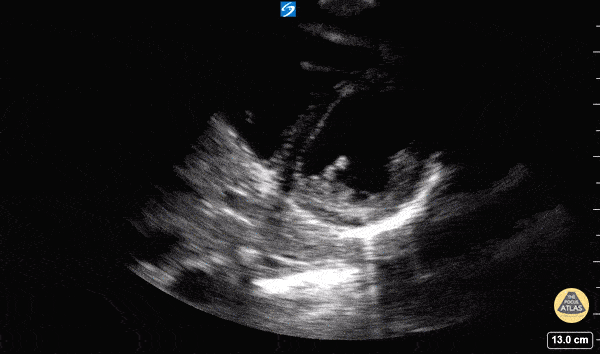

Normal Cardiac Anatomy - Parasternal Short Axis - Normal

In this view we are evaluating the heart in cross-section. In the center of the screen is the muscular walled left ventricle, which should form a perfect circle. This is at a level below the mitral valve and we can see the papillary muscles come into view. The smaller, thin walled, crescent shaped right ventricle is seen superficially and to the left of the screen. Hannah Kopinski - MS4, Dr. Lindsay Davis - NYU/Bellevue Department of Emergency Ultrasound, Dr. Matthew Riscinti - Kings County Emergency Medicine